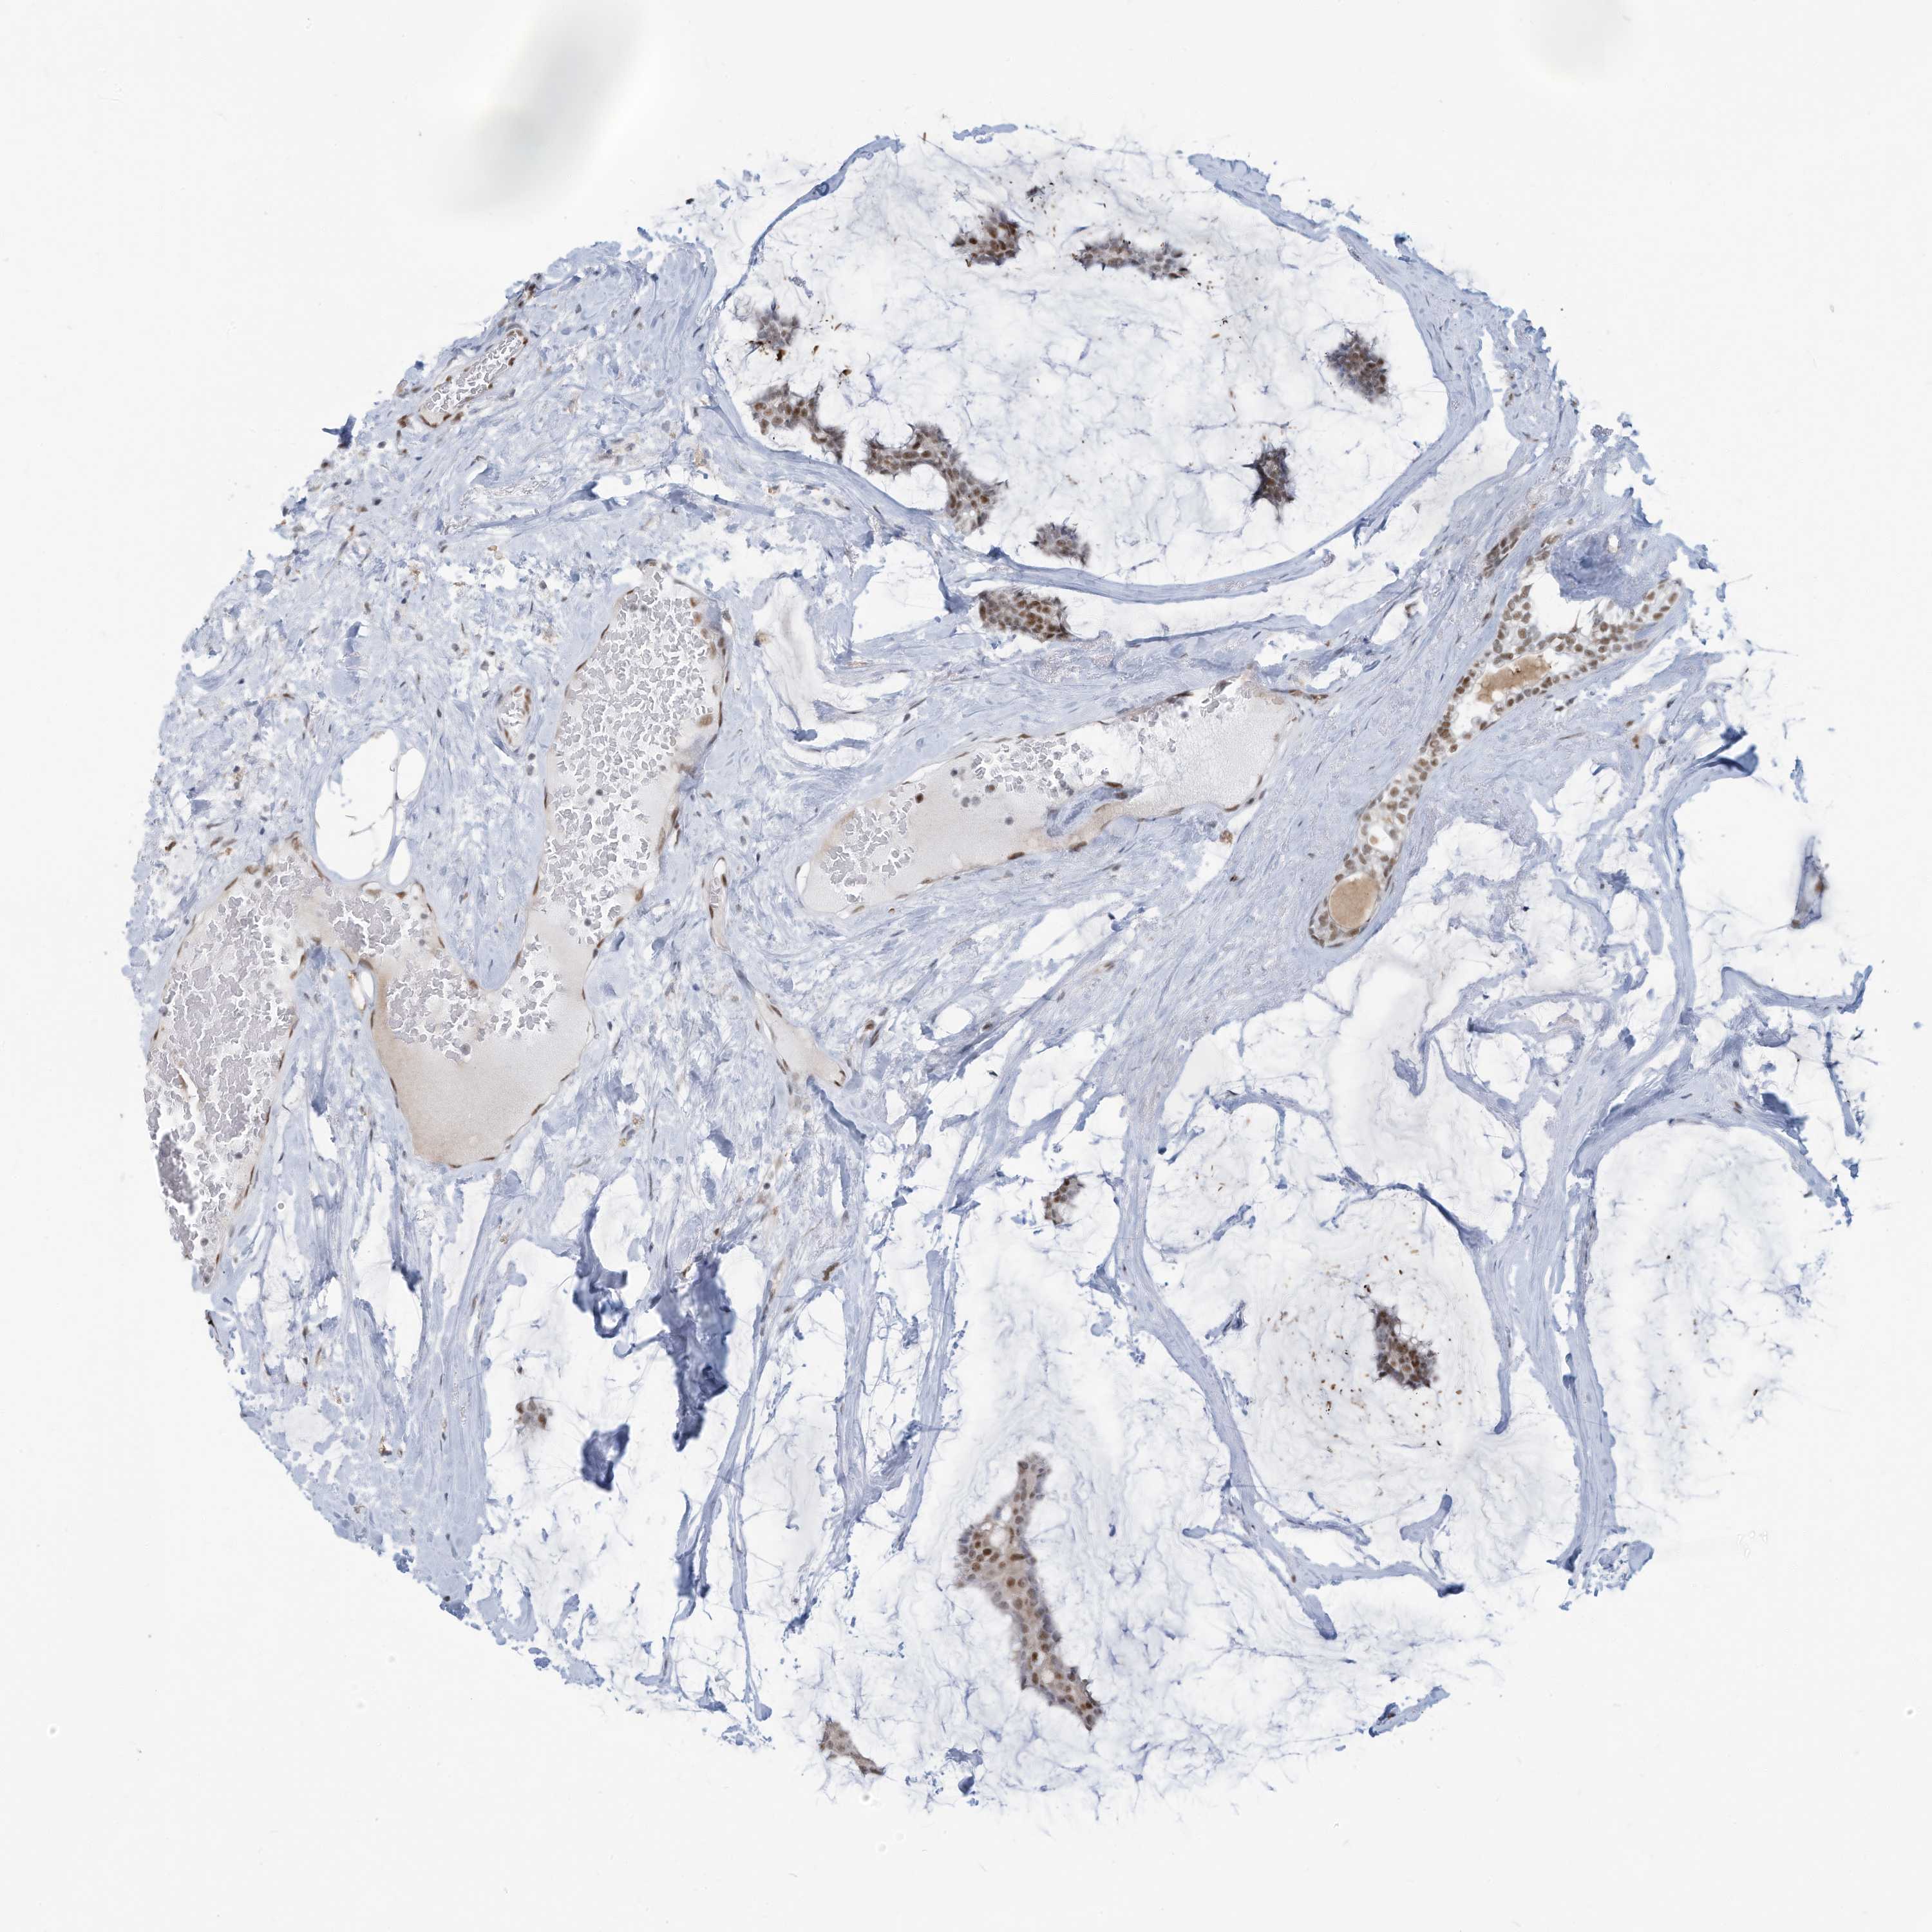

CANCER BREAST CANCER Show tissue menu

BRCA TCGA BRCA VALIDATION PROTEIN EXPRESSION

ANTIBODIES

AND

VALIDATION